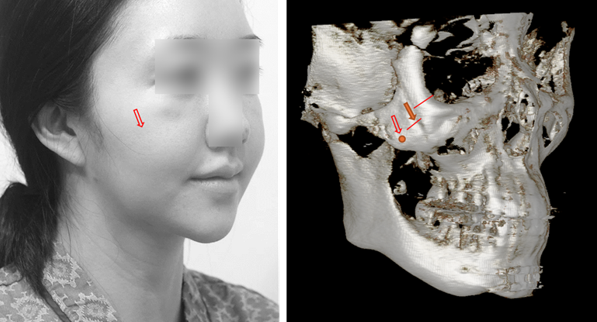

광대 수술 등 안면윤곽 후에 생긴 볼처짐은 노화와 양상이 완전히 다르기 때문입니다. 피부가 늘어난 것이 문제가 아니라, 수술 과정에서 뼈와 근육이 아래로 떨어지면서 그 위에 얹혀 있던 볼살의 위치가 함께 내려간 것이 주된 원인입니다.

잘못된 안면윤곽으로 볼살이 아래로 처졌을 때는, 원인은 볼살이 아닌 뼈와 근육입니다. 뼈와 근육을 위로 올려주면 볼살은 함께 위로 올라가게 됩니다.

유튜브나 광고를 보면 윤곽 수술 후에는 시술로 꾸준히 '관리'해야 한다고 말하는 이들을 흔히 볼 수 있습니다. 하지만 윤곽 수술이 잘못되어 발생한 볼처짐에서 실 리프팅이나 레이저 같은 시술은 근본적인 변화를 줄 수 없습니다. 잠시 덜 처져 보이는 효과로 마치 '관리'되는 것처럼 보일 뿐입니다. 살을 넓게 박리하고 잘라내어 당기는 안면거상은 그나마 이런 시술보다는 효과가 있기는 합니다. 그러나 윤곽 후 볼처짐의 원리를 고려하면, 일반적인 안면거상보다는 골막하 중안면 거상이 해부학적으로 더 적합한 선택지가 됩니다. 떨어진 옷걸이, 즉 뼈와 근육을 다시 본래 위치로 들어 올리는 방식이기 때문입니다.